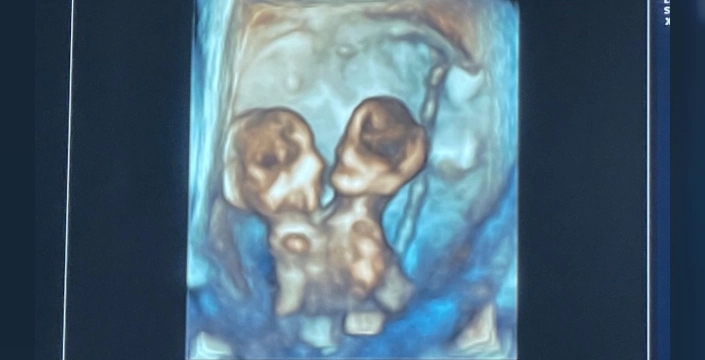

ABD'nin Michigan eyaletinde yaşayan Nicole ve Austin LeBlanc çifti, ilk kez bebek sahibi olacaklarının öğrenmesiyle büyük bir mutluluk yaşadı. Ancak, gebeliğin yedinci haftasında doktorlar, yalnızca bir kalp atışı duymalarına rağmen ultrasonda ikiz gördüklerinden şüphelendi. Kısa süre sonra Nicole, şiddetli karın ağrısıyla hastanenin acil servisine kaldırıldı ve yapılan ultrason sonucunda gerçek ortaya çıktı: Nicole, birbirine yapışık ve aynı kalbi, karaciğeri, bağırsakları, diyaframı ve göbek kordonunu paylaşan ikiz kız bebeklere hamileydi.

Annelerinin bu seçimiyle 32. haftada Maria Therese ve Rachel Clare sezaryenle dünyaya geldi. Nicole, doğum anını şöyle anlattı: 'Maria yüksek sesle ağladı, Rachel ise uyuyordu. Onların küçük yüzlerini ve paylaştıkları bedeni görmek inanılmazdı.' İkizler doğduktan hemen sonra anne ve babalarının kucağında hayata veda ettiler.